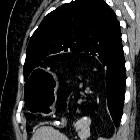

CT

Direct discontinuity of the hemidiaphragm may be seen with or without intrathoracic herniation of abdominal contents. The stomach and colon are the most common viscera to herniate on the left side and the liver is the most common viscus to herniate on the right side.

Other signs of diaphragmatic rupture include:

- the collar sign (or hourglass sign): a waist-like constriction of the herniating hollow viscus from the abdomen into the chest at the site of the diaphragmatic tear, which is classical for diaphragmatic rupture

- the dependent viscera sign: when a patient with a ruptured diaphragm lies supine at CT examination, the herniated viscera (bowel or solid organs) are no longer supported posteriorly by the injured diaphragm and fall to a dependent position against the posterior ribs

- segmental non-recognition of the diaphragm

- focal diaphragmatic thickening

- thoracic fluid abutting the abdominal viscera